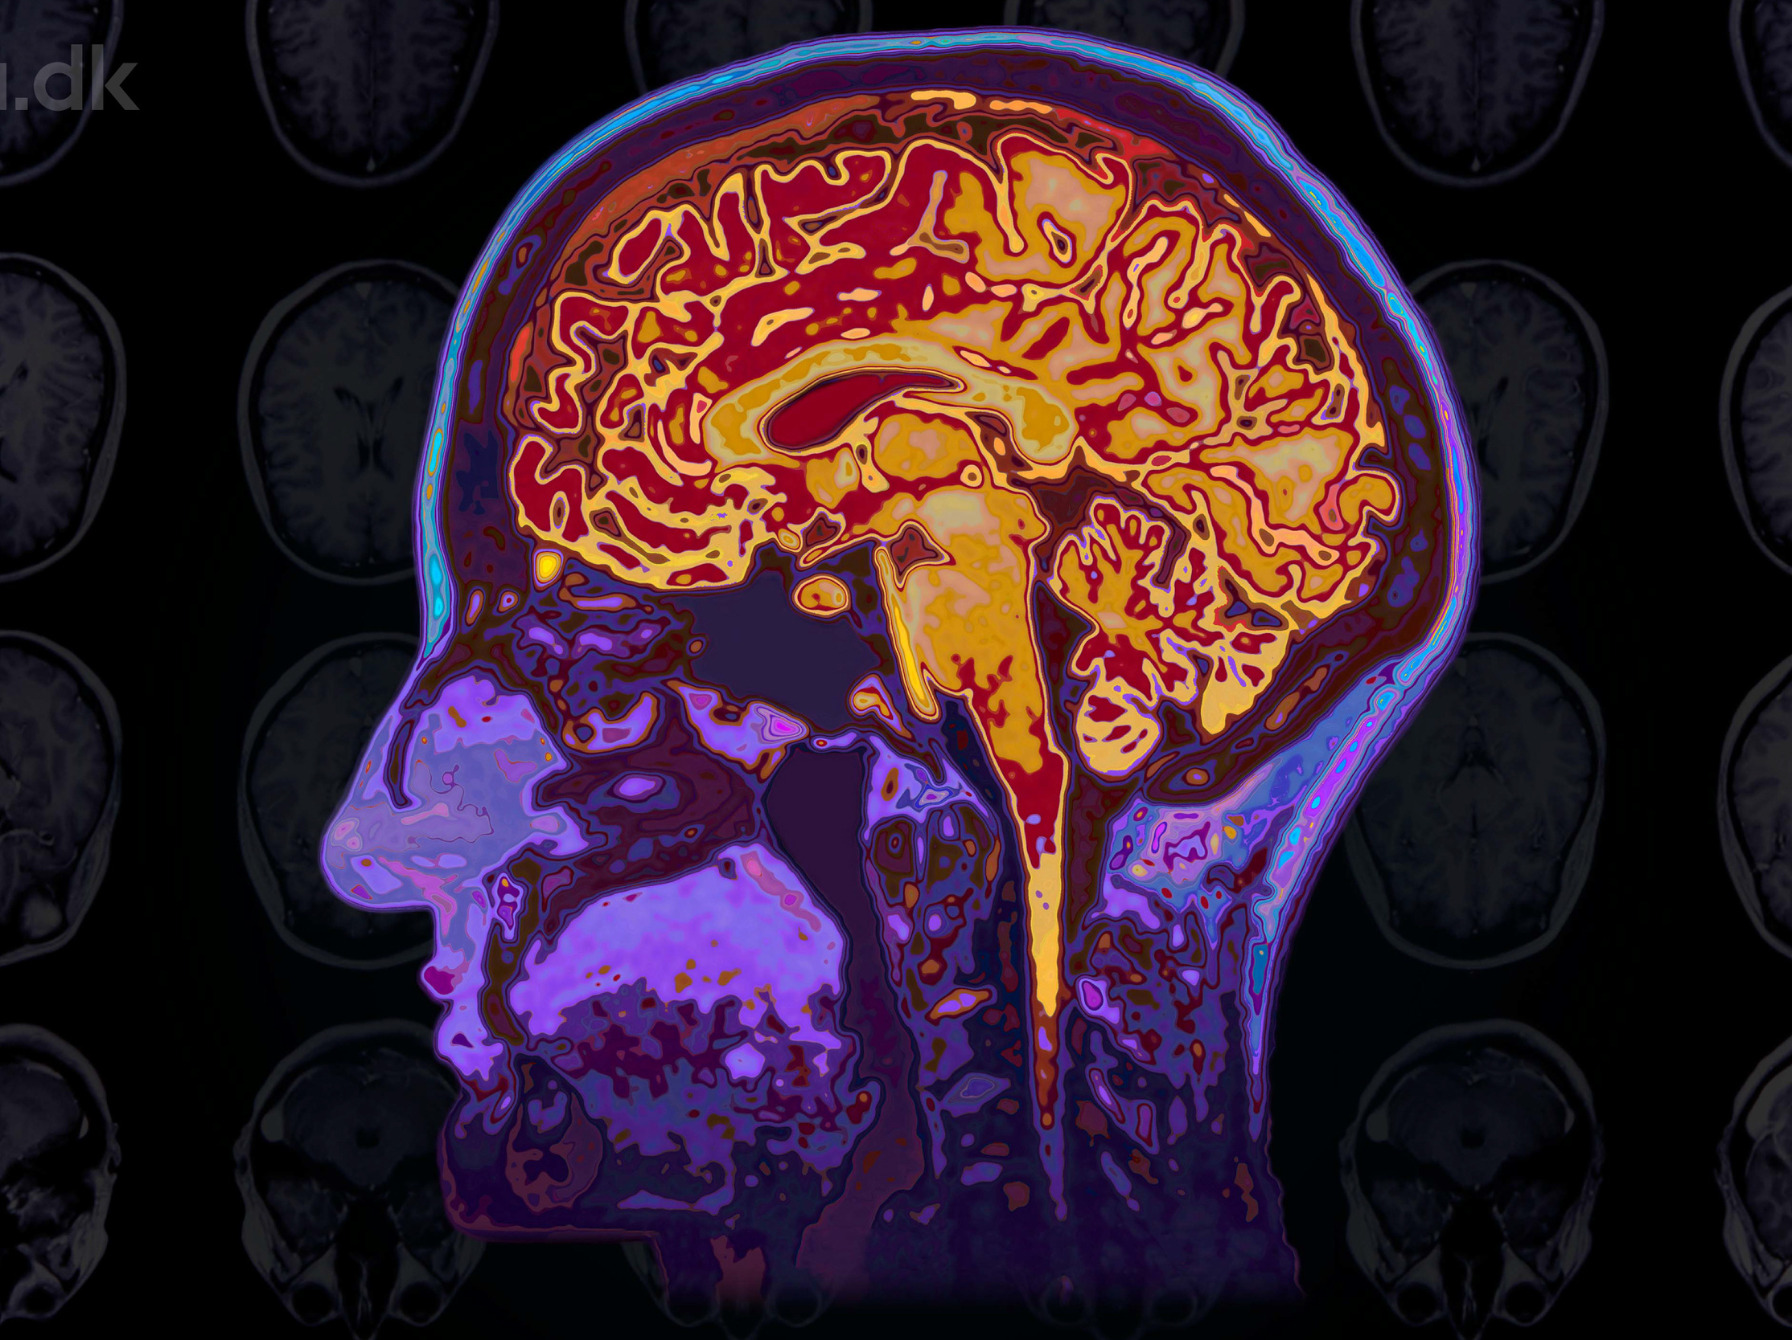

Foredraget vil give en indsigt i, hvordan musik og dans på tværs af kulturer kan skabe velvære og styrke sociale relationer. Ny forskning viser, hvordan musik, meditation og psykedeliske stoffer påvirker hjernen og kan føre til både forventningsglæde og meningsfylde.

Ved hjælp af computermodellering af hjerneskanninger afdækker forskningen betydningen af nydelser som natur, mad, babyer, musik, meditation og psykedeliske stoffer for vores livskvalitet. Foredraget vil diskutere, hvordan denne viden kan forbedre vores tilværelse.